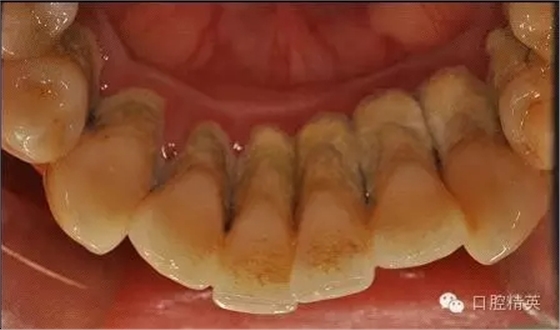

本病例 :女 34歲,主訴刷牙出血,覺(jué)牙齒輕度松動(dòng)一年。

檢查見(jiàn)大量齦上及齦下結(jié)石,探診出血,牙周袋較深,32-42 II度松動(dòng)。X線片顯示牙槽骨水平吸收。

診斷:成人慢性廣泛性中度牙周炎。

治療計(jì)劃:口腔衛(wèi)生宣教,刷牙指導(dǎo),齦上潔治,齦下刮治術(shù),下頜牙33-43牙周固定。

治療前: